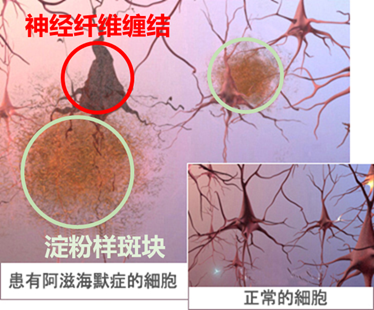

1 什么是阿兹海默症它是一种大脑疾病,为失智症的一种(失智症中约有6到8成是属于阿兹海默症),是一种不正常的老化现象也不是精神疾病。该病会导致记忆、思考与行为问题,初期以侵犯海马回为主,并随时间恶化,最终导致死亡,因病过世的患者脑解剖可发现异常老年斑及神经纤维纠结。[1][2]

形成的蛋白质小块会刺激免疫细胞导致发炎并吞食已丧失功能的细胞,使得突触被破坏。此外,Tau蛋白的过度磷酸化也会形成扭曲的神经纤维缠结,从内部阻塞神经元致使营养物质无法传送,最后使得细胞凋亡。

由于脑神经细胞的死亡与脑组织的损失,因此,阿兹海默症患者的脑部会逐渐萎缩以致影响所有的功能。